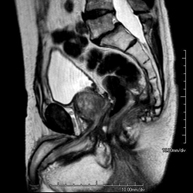

- Abdomen i pelvis

Prova diagnòstica no invasiva que consisteix en l'obtenció d'imatges d'alta definició anatòmica de l'abdomen mitjançant l'ús d'un camp electromagnètic i ones de ràdio (amb un emissor i un receptor). No utilitza radiació ionitzant. En aquesta exploració s'inclouen el fetge, el pàncrees, la melsa, la via biliar, la vesícula biliar, les glàndules suprarenals, els ronyons, l'aorta abdominal, la vena cava inferior, l'estómac, el duodè, etc. En alguns casos caldrà emprar contrast paramagnètic (Gadolini) per caracteritzar les lesions. - RM Pelvis femenina

Prova diagnòstica no invasiva que consisteix en l'obtenció d'imatges d'alta definició anatòmica de la pelvis mitjançant l'ús d'un camp electromagnètic i ones de ràdio (amb un emissor i un receptor). No utilitza radiació ionitzant. Es realitza per a l'estudi de patologies d'úter, d'ovari, de trompes i de vagina, ja siguin d'origen tumoral, inflamatori o vascular. També permet valorar les estructures adjacents localitzades a la pelvis i la identificació de les seves alteracions. De vegades és necessari l'ús de contrast intravenós (Gadolini) per caracteritzar les lesions. - RM Pelvis masculina